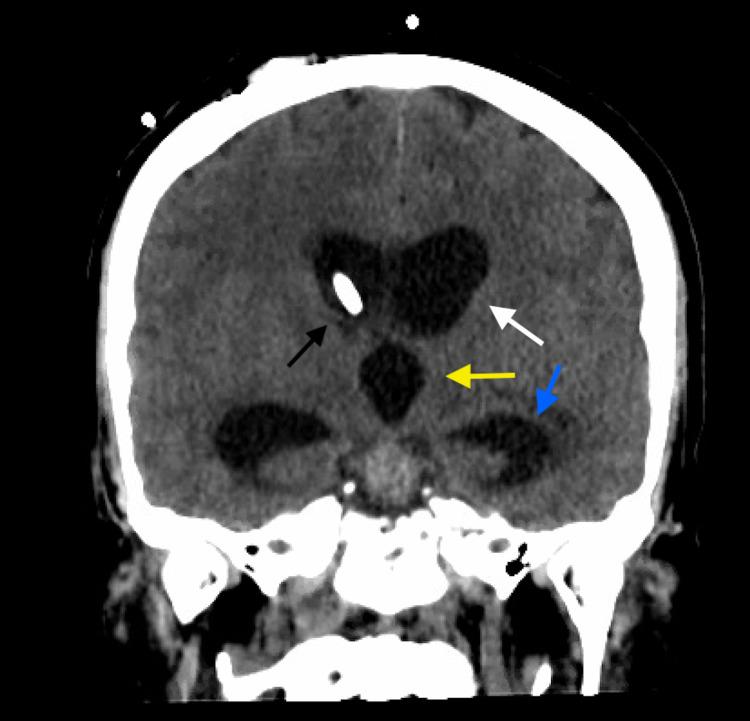

A preliminary report warned that severe acute respiratory syndrome coronavirus 2 (SARS-CoV-2) could have neuro-invasive potential as it was observed that some patients showed neurologic symptoms such as headache, nausea, and vomiting. Following early speculation there have been reports of neurologic manifestations involving both the central nervous system and peripheral nervous system including reports that coronavirus disease 2019 (COVID-19) may increase the risk of acute ischemic stroke. Here we present a patient with recent COVID-19 infection who experienced low-pressure hydrocephalus requiring high-output cerebrospinal fluid (CSF) diversion following spontaneous angiogram-negative subarachnoid hemorrhage. We hypothesize that patients who are either currently or who have recently been infected with SARS-CoV-2 may have altered ventricular compliance and/or altered CSF hydrodynamics from mechanisms that are not yet understood but potentially related to previously described pathophysiologic mechanisms of the virus and associated inflammatory reaction.

一份初步报告警告称,严重急性呼吸综合征冠状病毒2(SARS-CoV-2)可能具有神经侵袭潜力,因为观察到一些患者出现头痛、恶心和呕吐等神经症状。在早期猜测之后,有报道称神经系统表现涉及中枢神经系统和周围神经系统,包括有报道称2019冠状病毒病(COVID-19)可能增加急性缺血性中风的风险。在此,我们报告一名近期感染COVID-19的患者,该患者在自发性血管造影阴性蛛网膜下腔出血后出现低压性脑积水,需要进行高流量脑脊液(CSF)分流。我们推测,目前或近期感染SARS-CoV-2的患者可能存在心室顺应性改变和/或脑脊液流体动力学改变,其机制尚不清楚,但可能与该病毒先前描述的病理生理机制及相关炎症反应有关。